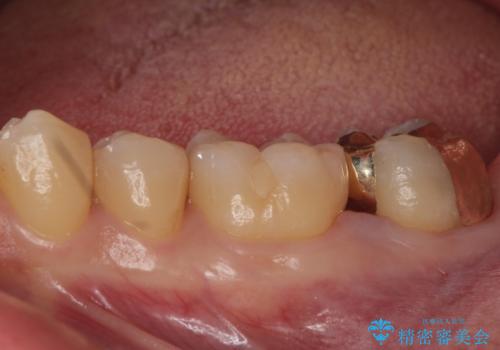

他院で入れたセラミックインレーが取れた。

- 他院で入れたセラミックの詰め物が取れてしまい来院。

適合を確認したところ、不適合だったため新しく形を作り直して、型取りをした方が良いことを説明した。

セラミックの詰め物で治療すると、詰め物の範囲が大きくなり、割れてしまう可能性があるので以下の治療の提案をした。

①ゴールドインレーによる治療

割れる心配がなく、歯質もセラミック治療よりも削らなくて済むが、審美的にセラミックより劣る。

②ジルコニアクラウンによる治療

白い被せ物を被せることで審美的に綺麗になり、割れるリスクが少ないが歯質を多く削ることになる。

二つの提案をしたところ、①を選択されたのでゴールドインレーによる治療を行いました。

- ゴールドインレー 11万円費用は治療当時の料金となります

ゴールドインレーは歯質との適合がよく

虫歯の再発リスクや割れるというリスクが低いです。

しかしご自身での口腔内ケアを怠っていると虫歯の再発リスクは高くなるので

定期的にメンテナンスにくることをお勧めします。